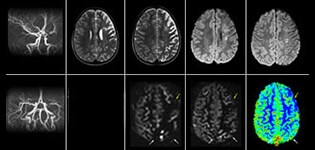

Pseudo-continuous arterial spin labeling (pCASL) was developed for brain perfusion imaging without contrast agent. “This is very desirable in pediatric patients where the general trend is to limit the administration of contrast,” says Dr. Miller. Growing confidence in specific applications “We built up confidence in pCASL by comparing it to contrast-based perfusion imaging. Once we had confidence that it was representing what the contrast perfusions were representing, we increased our diagnostic confidence by serial imaging in either the acute stage or the long term stages in a number of patients with arterial abnormalities.

Dr. Miller uses pCASL for all patients who present with chronic and acute cerebrovascular abnormalities such as acute stroke, as well as patients who present with signs of acute inflammation in the brain, and occasionally in patients with tumors, to assess the perfusion status of their tumor.

“In combination with diffusion weighted imaging, it can help give a more extended assessment of the degree of perfusion abnormality in a patient who is suffering acute ischemia. We have a number of patients who have chronic arterial insufficiency due to prior arterial abnormalities or acquired arterial abnormalities such as sickle cell disease or neurofibromatosis. Sometimes the child’s first manifestation of disease progression is a reduction in brain perfusion before stroke symptoms manifest clinically or in diffusion weighted imaging. We use pCASL to help delineate the perfusion abnormality.”

To other new users I would recommend to also start to interpret the pCASL images in comparison with other standard imaging – T2 and FLAIR and DWI – until the user gains confidence in interpreting these images by themselves.” “A powerful use of pCASL is in patients with chronic cerebrovascular stenosis, where clinicians desire information on how compensatory mechanisms of the brain are performing to enable perfusion to the brain. Often clinicians take into account how the compensatory mechanisms appear to help to provide adequate perfusion to the patient’s brain, and they may intervene surgically or make some other management decision.” “Another special application is the assessment of cerebrovascular reactivity with a Diamox perfusion exam, where we subtract two sets of pCASL images.”

“pCASL has now become more of a first-line scan for assessing perfusion for us, as opposed to DSC-based perfusion imaging with contrast agent. And in patients who were not planned to have contrast, we can perform pCASL for perfusion imaging without need to stop the exam, pull the patient out, and put in an IV. It also negates the postprocessing that’s necessary for dynamic susceptibility contrasts. And it allows us to repeat perfusion imaging in the same patient at the same imaging time, which is helpful in terms of patient motion, or in a situation where a scan needs to be done before pharmacological perfusion imaging.”